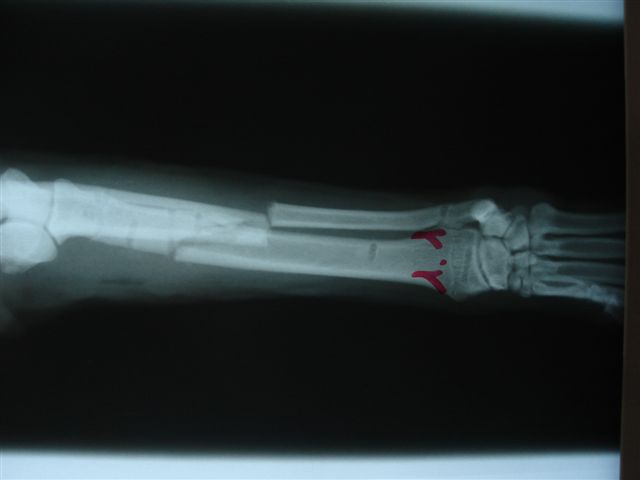

Fijación Externa en IVOT

Fijación Externa

IX CURSO BASICO DE FIJACION EXTERNA.

Casos prácticos alumnos.